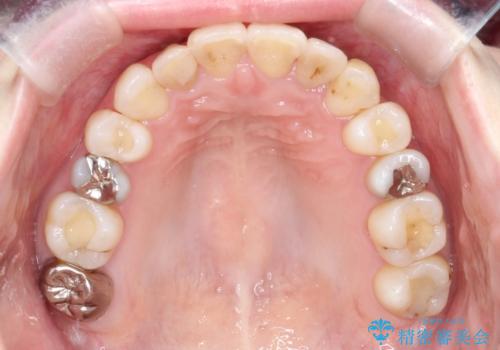

初診時の歯並びの状態としては、上下ともに前歯部中心としたの中等度のがたつき(叢生)があり、全特に左上の前歯は1本だけ引っ込んでおり、犬歯は外に飛び出した状態でした。

抜歯は行わず上顎の奥のスペースを利用して歯をスライドする方法の他に歯列弓の拡大やディスキング(歯と歯の間の隙間を作る処置)を行い叢生を改善しましています。

歯の大きさの不揃いが原因の正中のズレは、ディスキング量を調整することで合わせました。

見た目、嚙み合わせ及び、治療期間や施術内容に大変ご満足いただきました。